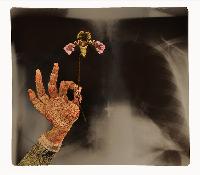

Изучение проблемы низкого качества рентгенограмм на Вашем оборудовании.

Мобильный рентгенаппарат + оцифровщик. Получение рентгеновского изображения на экране ноутбука. Вариант за 1,4 миллиона рублей под ключ.

Мобильный рентгенаппарат с печатью рентгенограмм на рентгеновской пленке. Цена 700000 рублей.